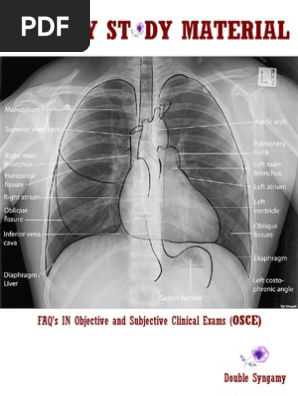

Mock Oral Cases Heart Thorax

Medical Student Surgery Osce

Surgery Osce Questions Medical Specialties Clinical Medicine

How To Assess The Post Operative Surgical Patient Osce Guide